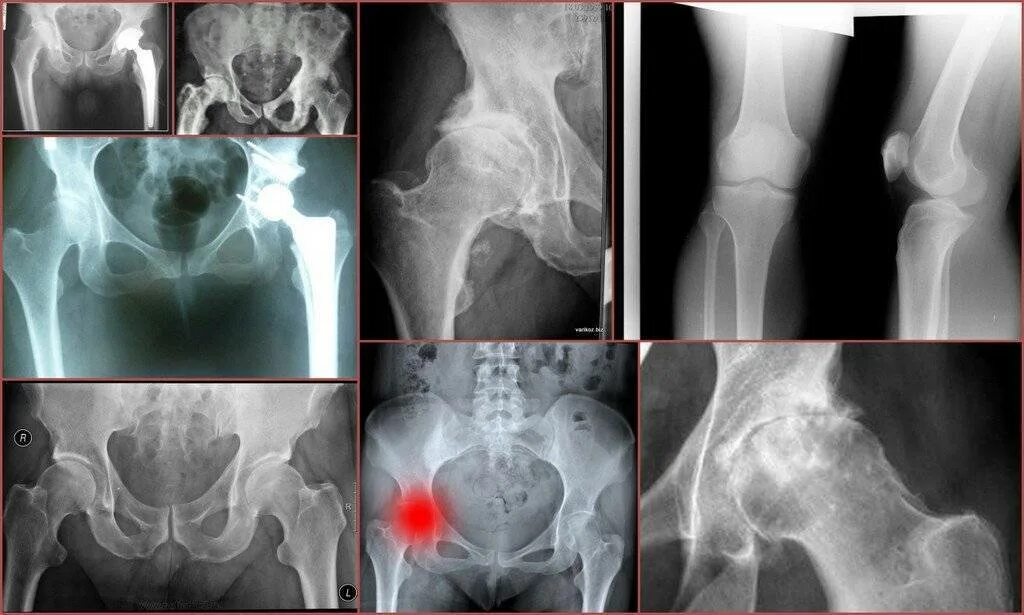

Тазобедренный сустав 3 степени лечение